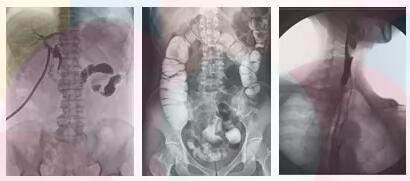

在胃腸檢查過程中即可獲得流暢的動態(tài)影像,又可獲得高清晰的靜態(tài)影像,完整的將患者影像進行數(shù)字化存儲 ,便于后期的復查和對比。

方面三、子宮輸卵管造影,優(yōu)選動態(tài)平板dr

采集面積大,一次曝光即可顯示整個盆腔,大幅減少觀察時間,可控的瞬時照射避免受檢者吸收過多的X線,對育齡期婦女的檢查尤為重要。實時高清點片,可以在造影劑流動的過程中完成拍片,抓拍到關鍵圖像,清楚的了解管腔的具體通暢情況及堵塞部位,對檢查及診斷有非常重要的價值。